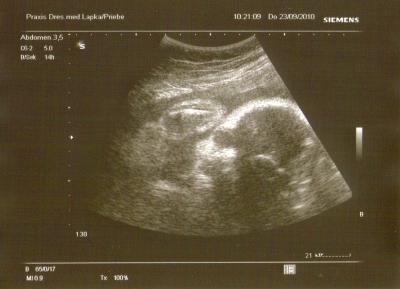

So, ich hatte ja eben schon von der erfolgreichen VU heute berichtet, dann will ich noch schnell das neue Bildchen einstellen! Ein freundliches Kind, sieht aus als würde es winken, allerdings sieht das rechte Auge auf dem Ultraschall-Bild aus als wäre es größer als das Linke (wie ein kleiner Alien ) war auf demBilschirm aber nicht so! Ich bin ja sooooo gespannt wie Krümel im Original aussieht Wünsche Euch allen einen schönen Abend und eine ruhige Nacht mit vieeeel Schlaf!

Bild zu Neues Krümel-Portrait! - Forum für November - Mamis